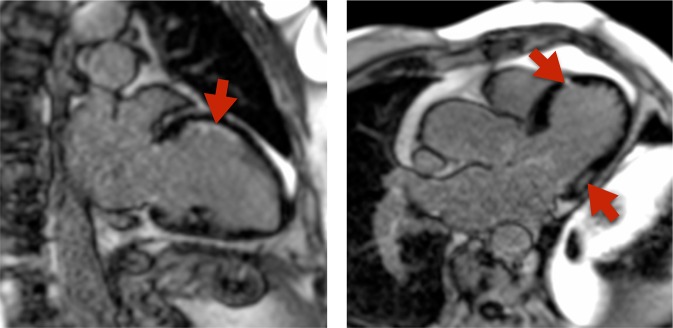

Figure 1.

Cardiac magnetic resonance (CMR) examples of cardiac fibrosis involvement in primary carnitine deficiency (PCD). Arrows shows late gadelineum involvement representing cardiac fibrosis.

Two c.95 A > G homozygous PCD patients had unexplained myocardial LGE (Fig. 1). One patient had LGE in the midmyocardium in the basal inferolateral segments, and the other patient had LGE in the midmyocardium in the lateral midventricular segment. A third elderly c.95 A > G homozygous patient had subendocardial LGE (50% transmurality) in the anterior segments, however the pattern was consistent with his history of previous myocardial infarction, and hence was not included in the analysis. There were no findings of myocardial LGE in any of the other patients, carriers nor healthy controls (p = 0.10).